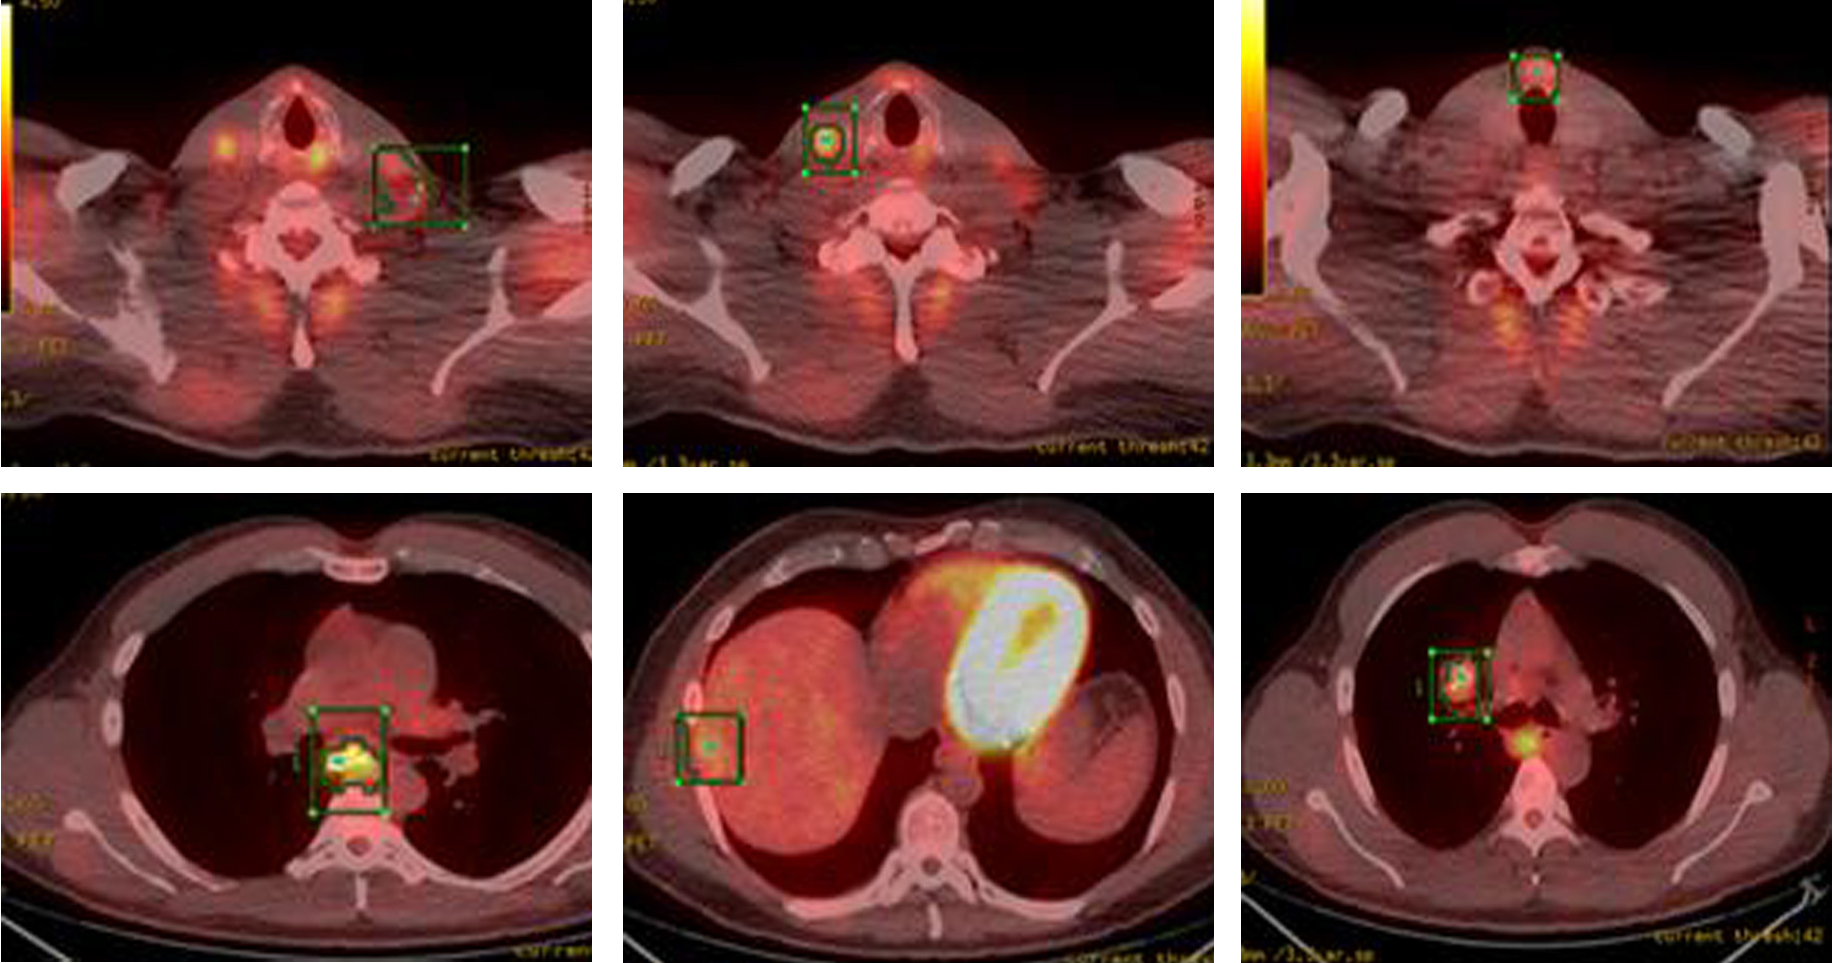

Whole body PET-CT showed a calcified right suprahilar mass with SUV of 3.1. Mildly patchy FDG-avid uptake in the liver with multiple pulmonary nodules involving both lungs was seen. Sclerotic changes in the skeleton suspicious for osseous metastasis were also noted (Fig. 3). Patient was also tested for RET gene mutation and was found to be negative for the same. Serum catecholamines were within reference range.

![]() Click for large image | Figure 3. PET-CT showing FDG-avid nodular lesion in the thyroid isthmus, multiple bilateral cervical nodes, calcified mediastinal and hilar mass, patchy uptake in liver and sclerotic changes in skeleton suspicious for osseous metastasis. |